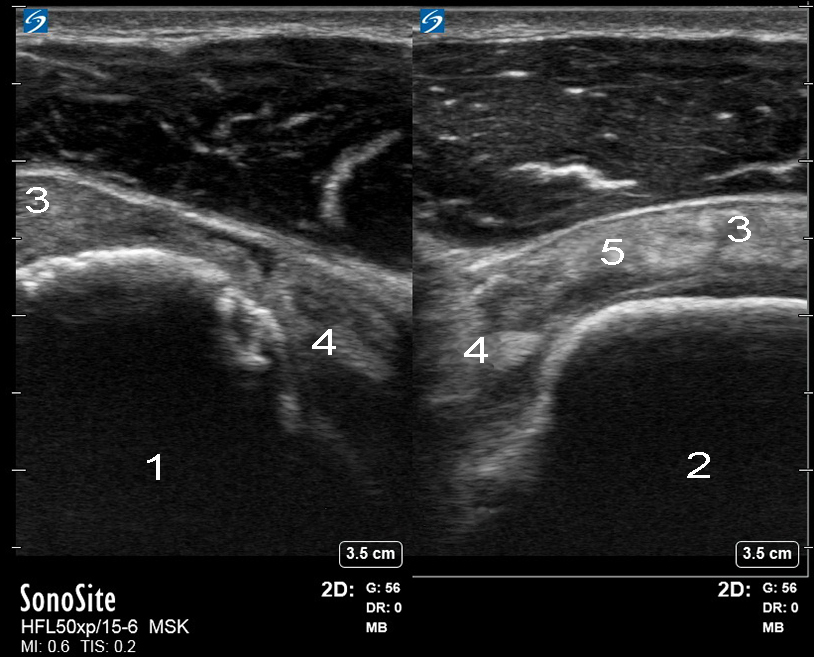

肩袖损伤图像

肩袖间隙

右

左

冈下肌

二头肌腱 (BT)

冈上肌